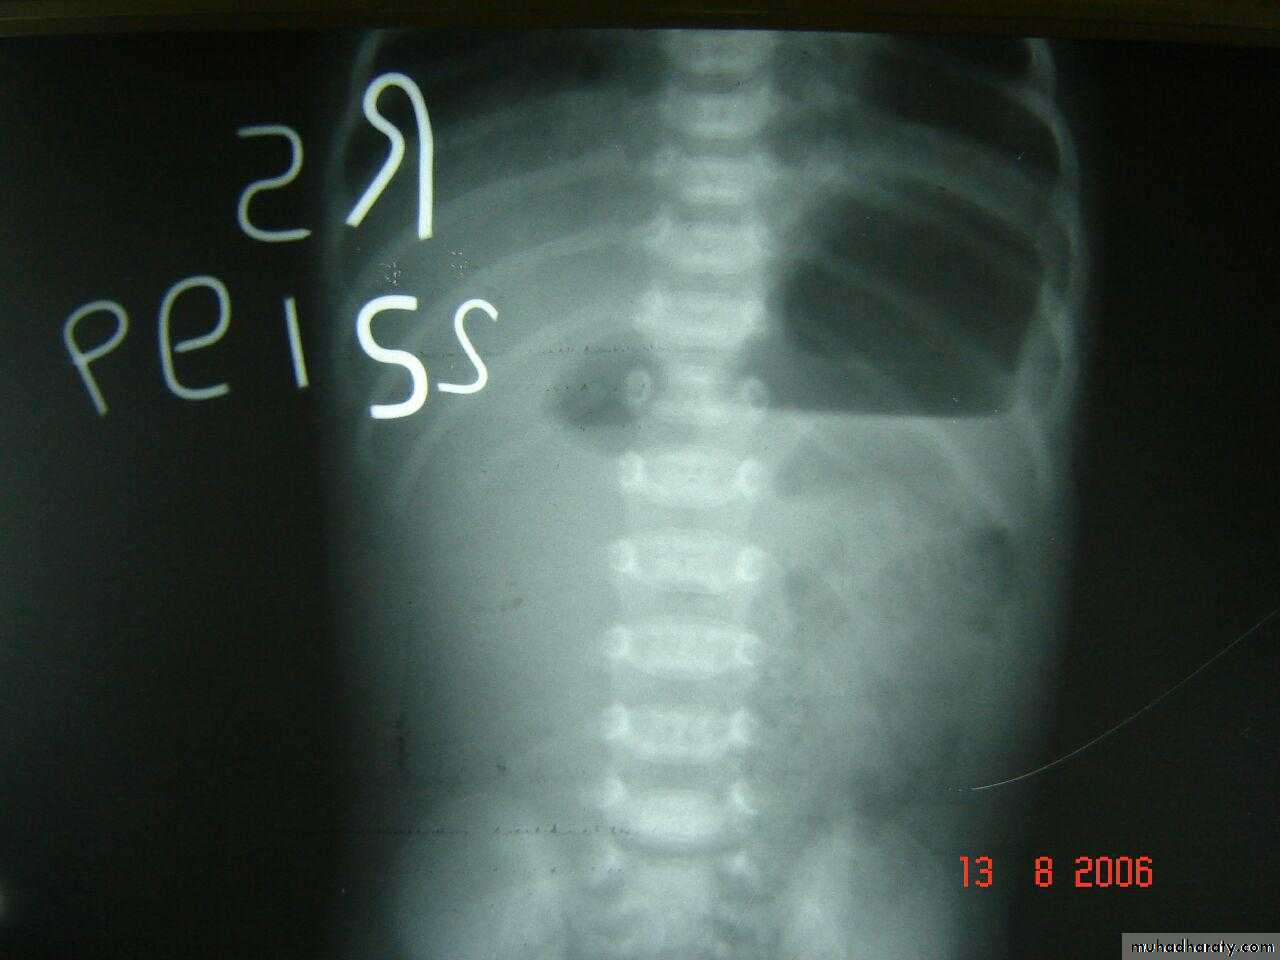

Deudenal obstruction double bubble sign

Rx iv fluid , surgeryDouble bubble sign deudenal obstruction + air fluid level

Double bubble apperance of dudenal atresia